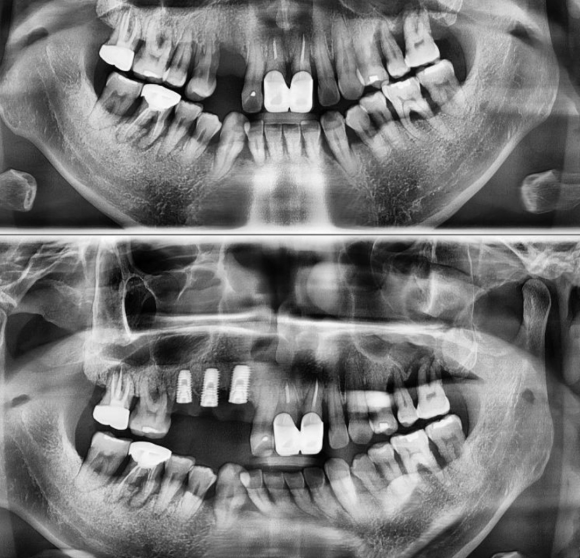

재난 영화를 보면 땅이 무너지고 건물이 쓰러지듯..

전체적인 잇몸(땅)이 무너져내리고 염증이 심해서

대부분의 치아를 발치하고

광범위한 임플란트가 필요한 케이스 입니다.

비용 문제로 일단 가장 심한 3개부터 시작 했습니다.

잇몸상태가 매우 좋지 않아서 임플란트 이후에도

이미 가지고 있는 습관과 치주 문제로 임플란트가 세균감염에 매우 취약한 상태가 될 수 있지만

끝까지 치료를 잘 해드리고 예방목적 치과 방문을 유도하고 강조해서

평생 잘 쓸 수 있도록 유도할 예정입니다.